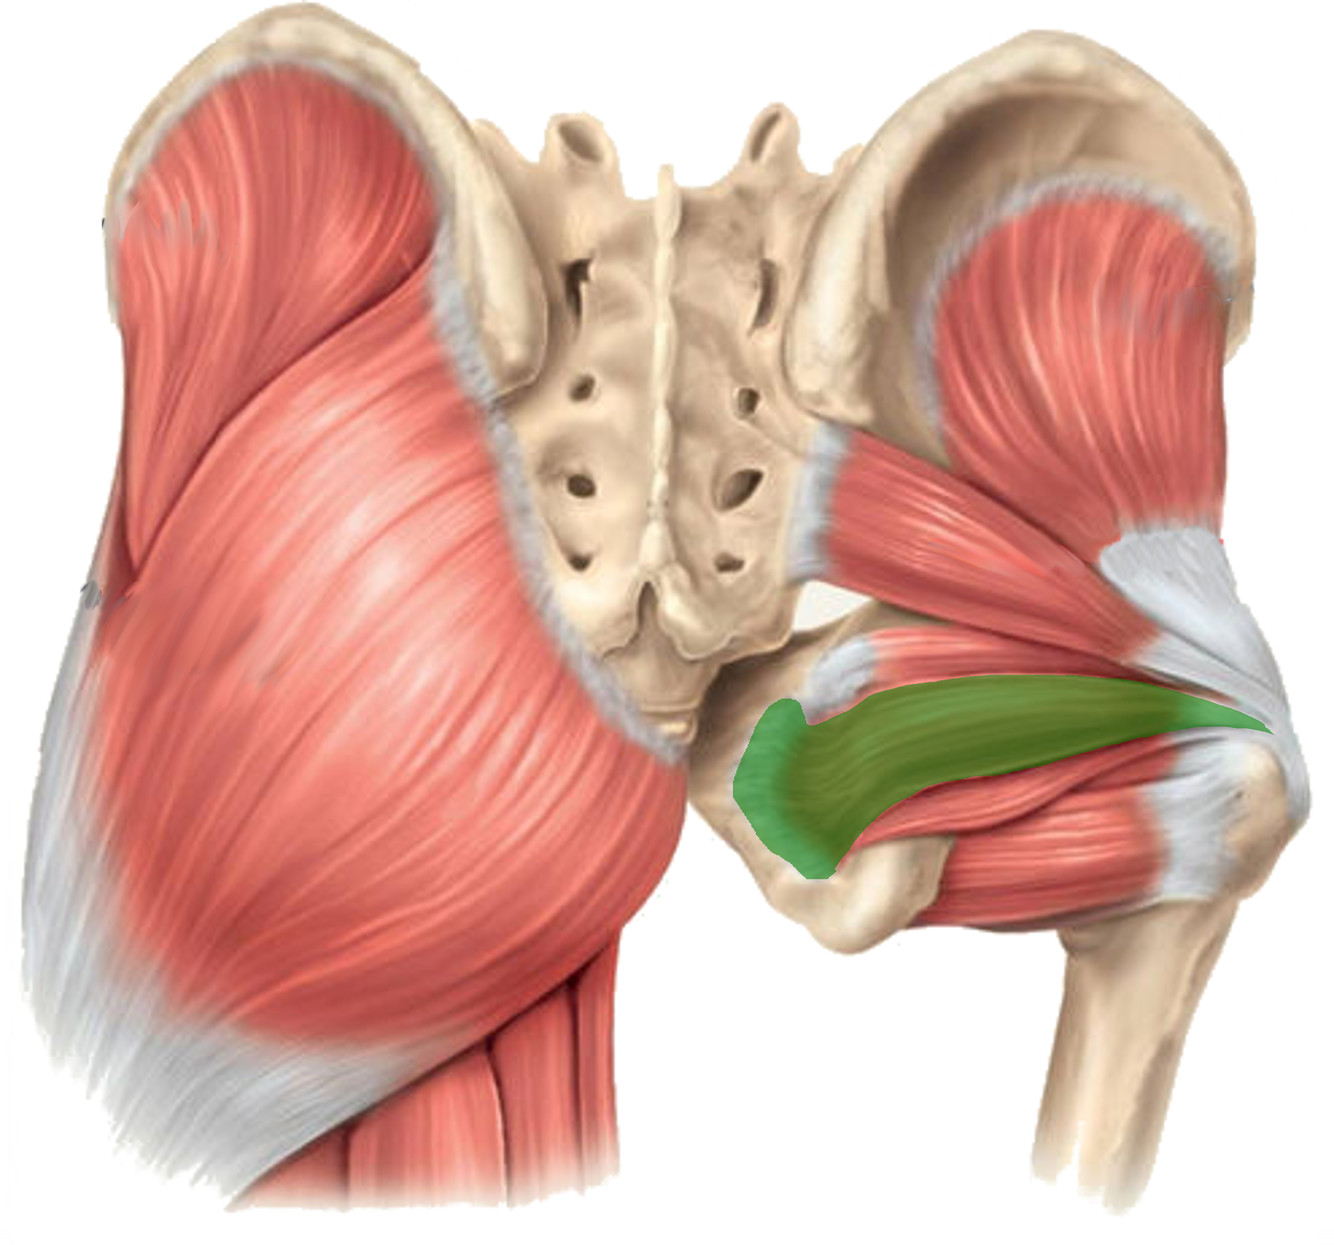

What is the innervation of this muscle (nerve roots)?

Muscle - Obturator internus

L5 + S1